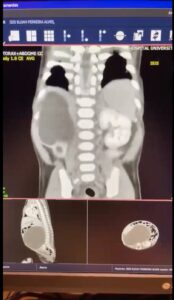

“Mais ou menos 10% de todas as crianças que nascem no mundo inteiro vão ter alguma malformação congênita, que podem acontecer em todos os órgãos do corpo humano. No caso de Isis, o quadro estava relacionado à estrutura que dá origem aos rins. A menina nasceu com quatro rins ao todo, dois em cada lado do corpo, sendo que os rins inferiores estavam ligados. A condição é chamada de ‘rins em ferradura’, por causa do formato adotado pelos órgãos unidos, mas que não oferece riscos a Isis.”

O fato de uma criança nascer com mais de dois rins, por si só, não é um problema. Porém, um dos rins de Isis estava obstruído, causando um inchaço que prejudicava os órgãos vizinhos. “Esse rim estava tão grande que impedia os outros órgãos de funcionar a contento. O intestino dela, o diafragma e os pulmões estavam completamente comprimidos por essa grande massa”, conta Buson.

O médico Hélio Buson urologista-pediátrico explica que um dos rins “estava tão grande que impedia os outros órgãos de funcionar a contento. O intestino dela, o diafragma, os pulmões estavam completamente comprimidos por essa grande massa” | Imagem: Captura de Tela/HCB